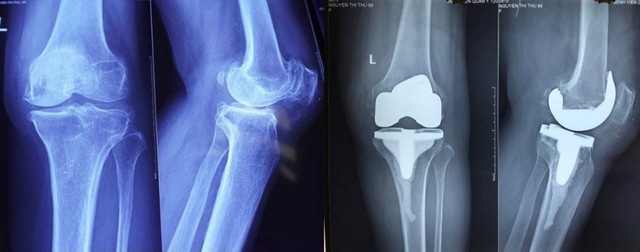

צילומי רנטגן של המטופל לפני ואחרי הניתוח

"מפרק הברך השמאלי של המטופל נגוין טי טו ניזוק לחלוטין עם סחוס פגום ועיוות עצם, והוחלף במפרקי ברך מלאכותיים מהדור האחרון שמקורם בארצות הברית. הניתוח עבר בהצלחה ובטוח. לאחר הניתוח, המטופל יקבל הדרכה פיזיותרפיה וישוחרר תוך מספר ימים", הוסיף ד"ר טראן דאנג קואה.